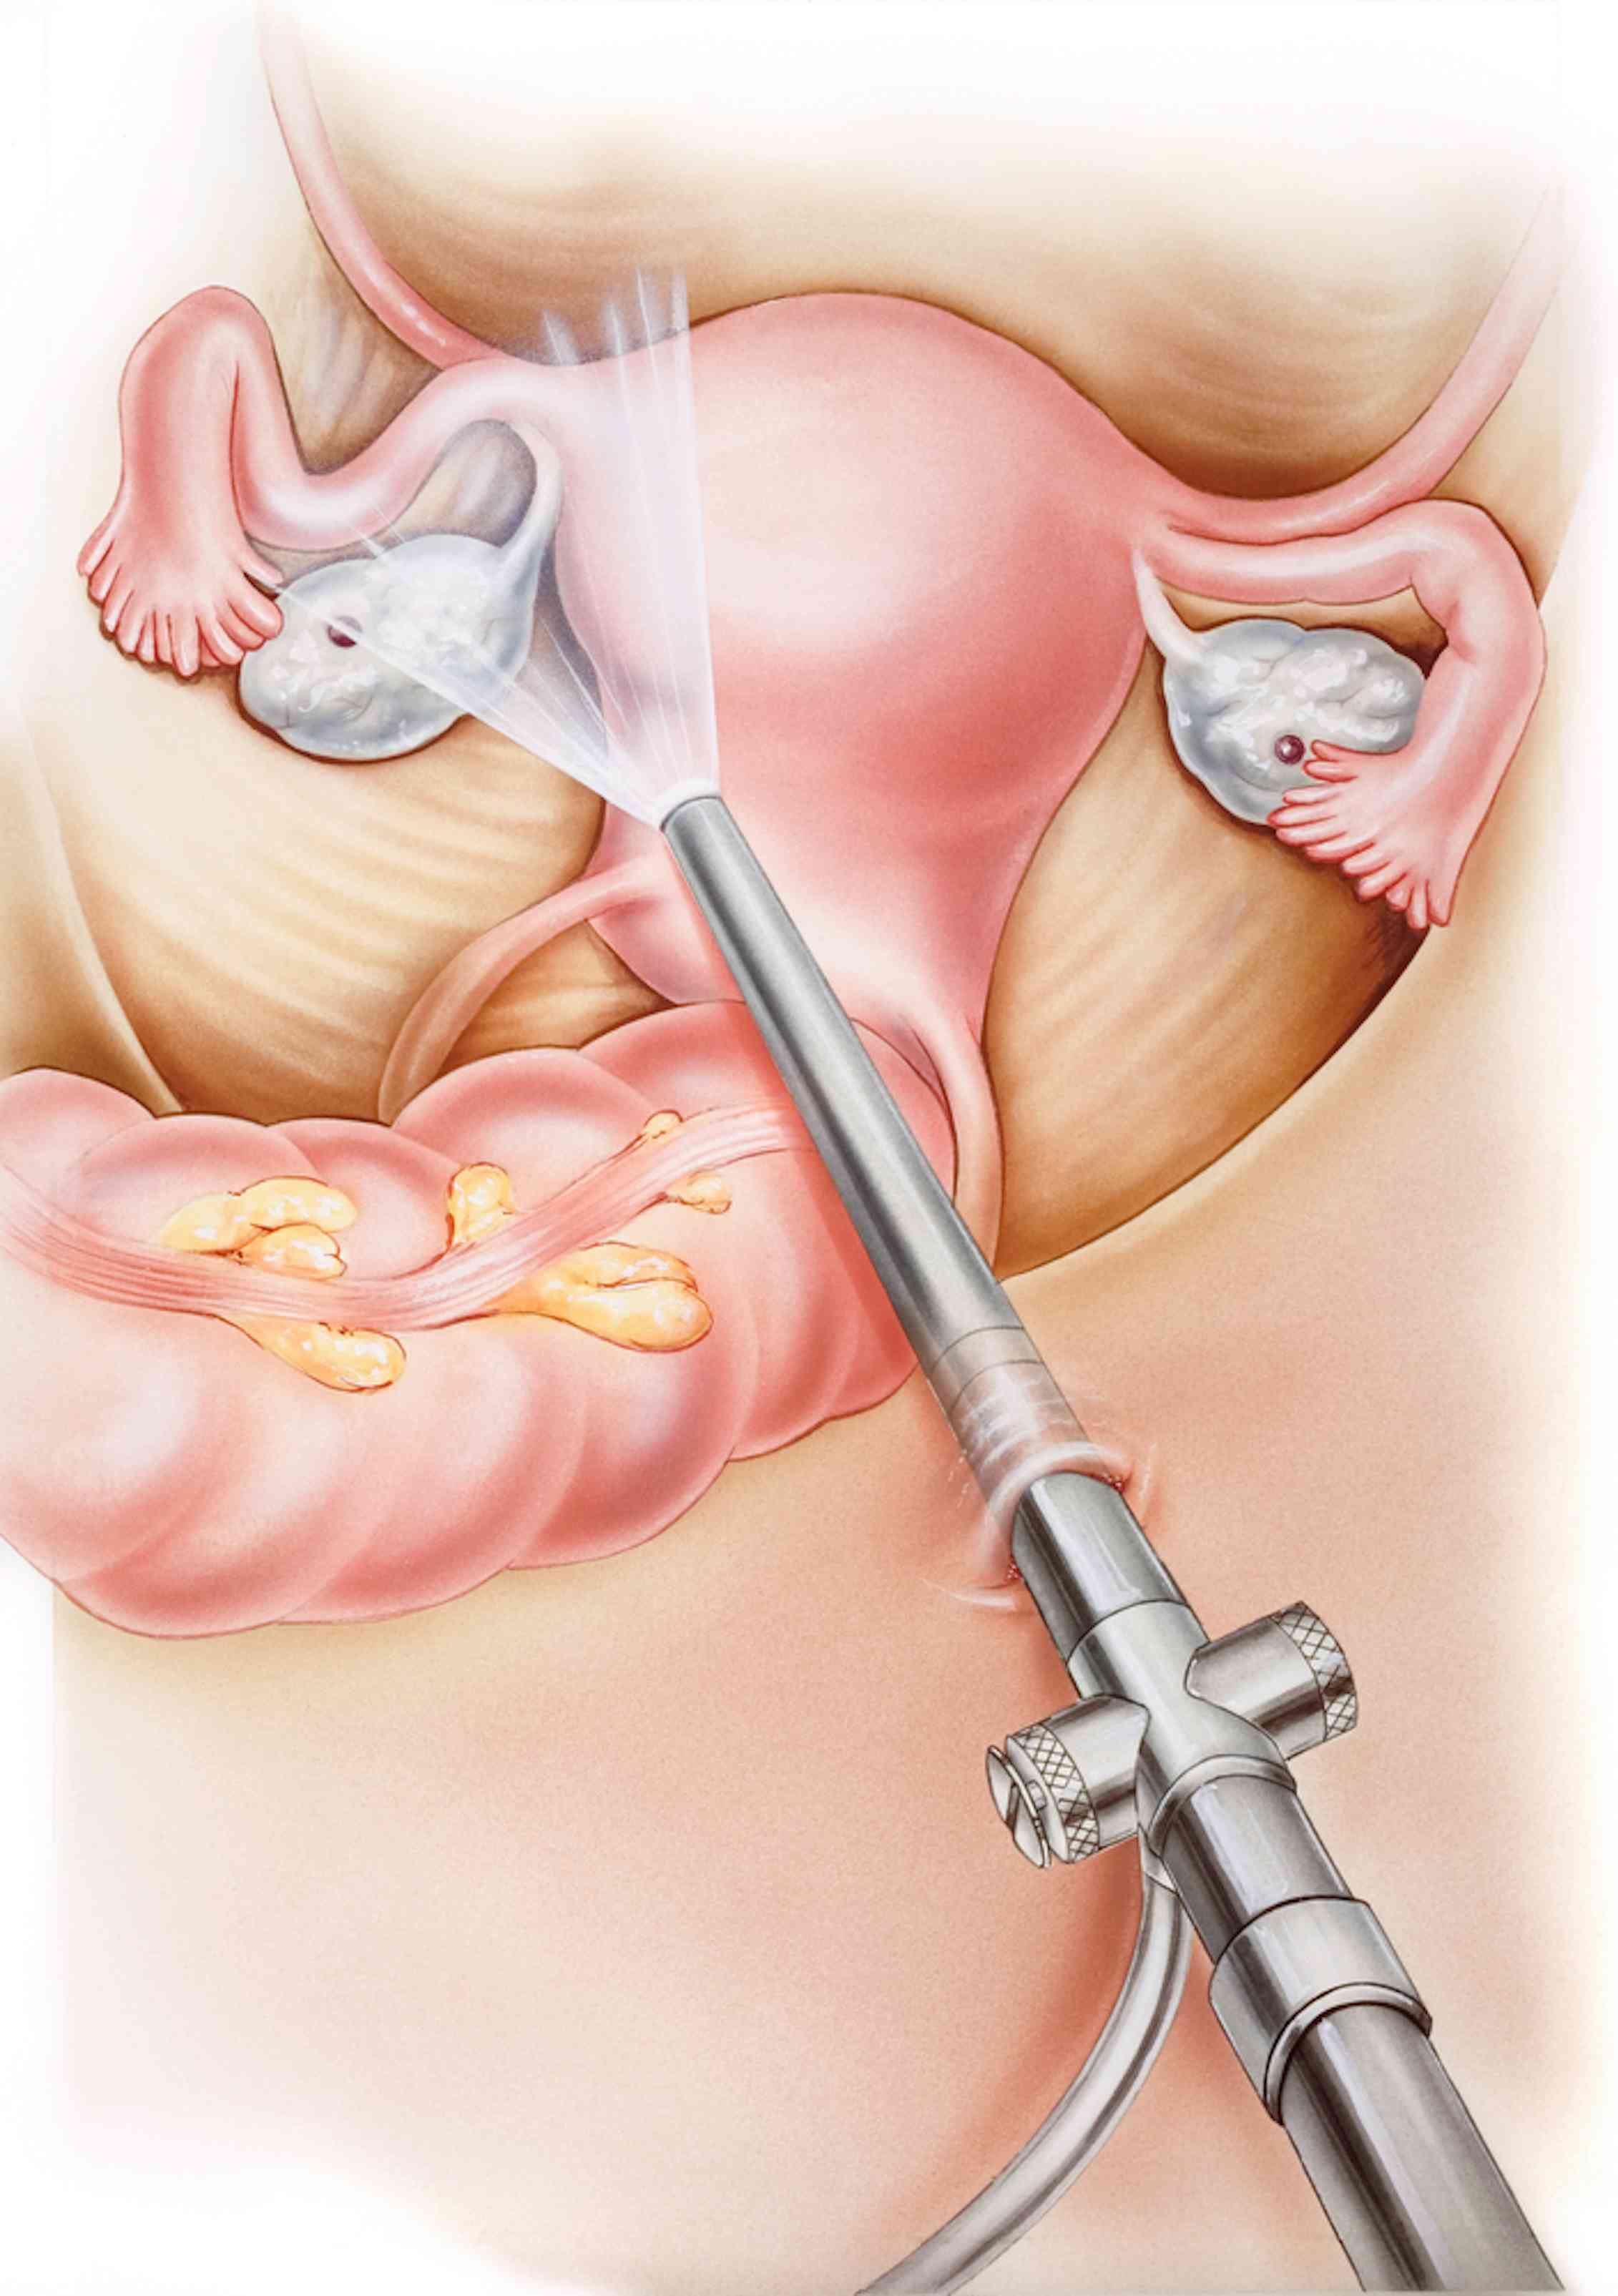

Современные методы лапаротомии и миомэктомии